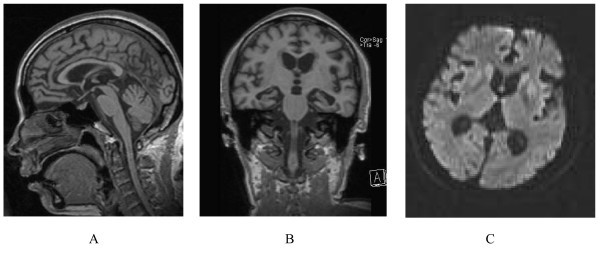

Human Prion Disease With A G114V Mutation And Epidemiological Studies

Human prion disease with a G114V mutation and epidemiological studies jmedicalcasereports.biomedcentral.com

prion prioni gss atrofie mutation epidemiological